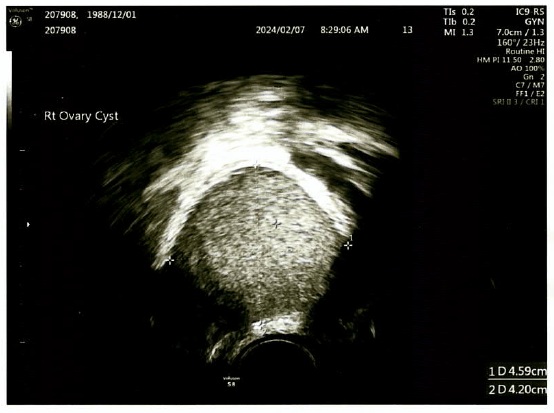

▲超音波圖。(圖/茂盛醫院提供)

有鑑於王小姐還想備孕,林醫師決定採用「單孔微創腹腔鏡手術」(註2)進行切除。她的卵巢右側有3顆畸胎瘤全部擠在一起,分別為4公分、3公分、2公分大;而左側則有1顆4公分的畸胎瘤。林醫師說,王小姐算是畸胎瘤較多的案例,一般臨床上較常見的是單側1顆或左右各1顆而已。研判她的畸胎瘤應屬良性,所以採用最不傷卵巢、傷口小、出血量也小的「單孔微創腹腔鏡手術」來解除她的病灶。結束休養後,就開立3個月的排卵藥,協助王小姐將原先不按牌理出牌的經期調好,果不其然,她吃完藥就自然受孕,且孕期都非常平順,直到二寶平安出生,母子兩人都很健康。